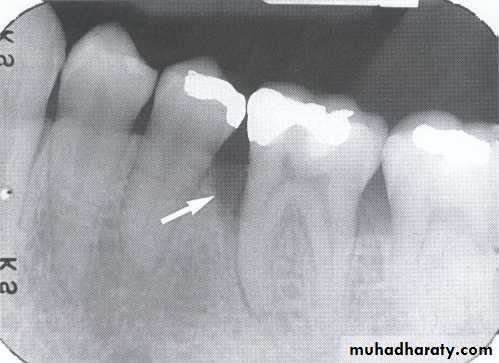

• B-Defective Restoration;

• Faulty dental restoration act as potential food traps & lead to the accumulation of food debris & bacteria.

• Radiographically; the defective filling identified with open or loose contacts, poor contour, uneven marginal ridges over-hangs.

caries

Overhang rest.